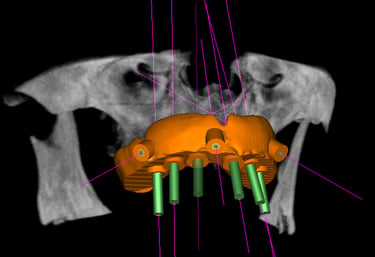

É possível planejar e fazer implantes dentários sem a necessidade de cortes ou bisturis. Utilizando a tecnologia digital, o procedimento se torna mais preciso e menos invasivo.

O planejamento é feito em um computador com base em tomografias e escaneamentos da boca do paciente. Com esses dados, um guia cirúrgico é impresso em 3D. Esse guia se encaixa na boca do paciente e mostra o local e o ângulo exatos para a inserção do implante, evitando a necessidade de abrir a gengiva com bisturi.

Planejamento digital do implante

O planejamento digital permite fazer a cirurgia sem bisturi e em poucos minutos.

Planejamento virtual feito sobre um modelo escaneado da boca do paciente. Fazendo os procedimentos serem de maior precisão.